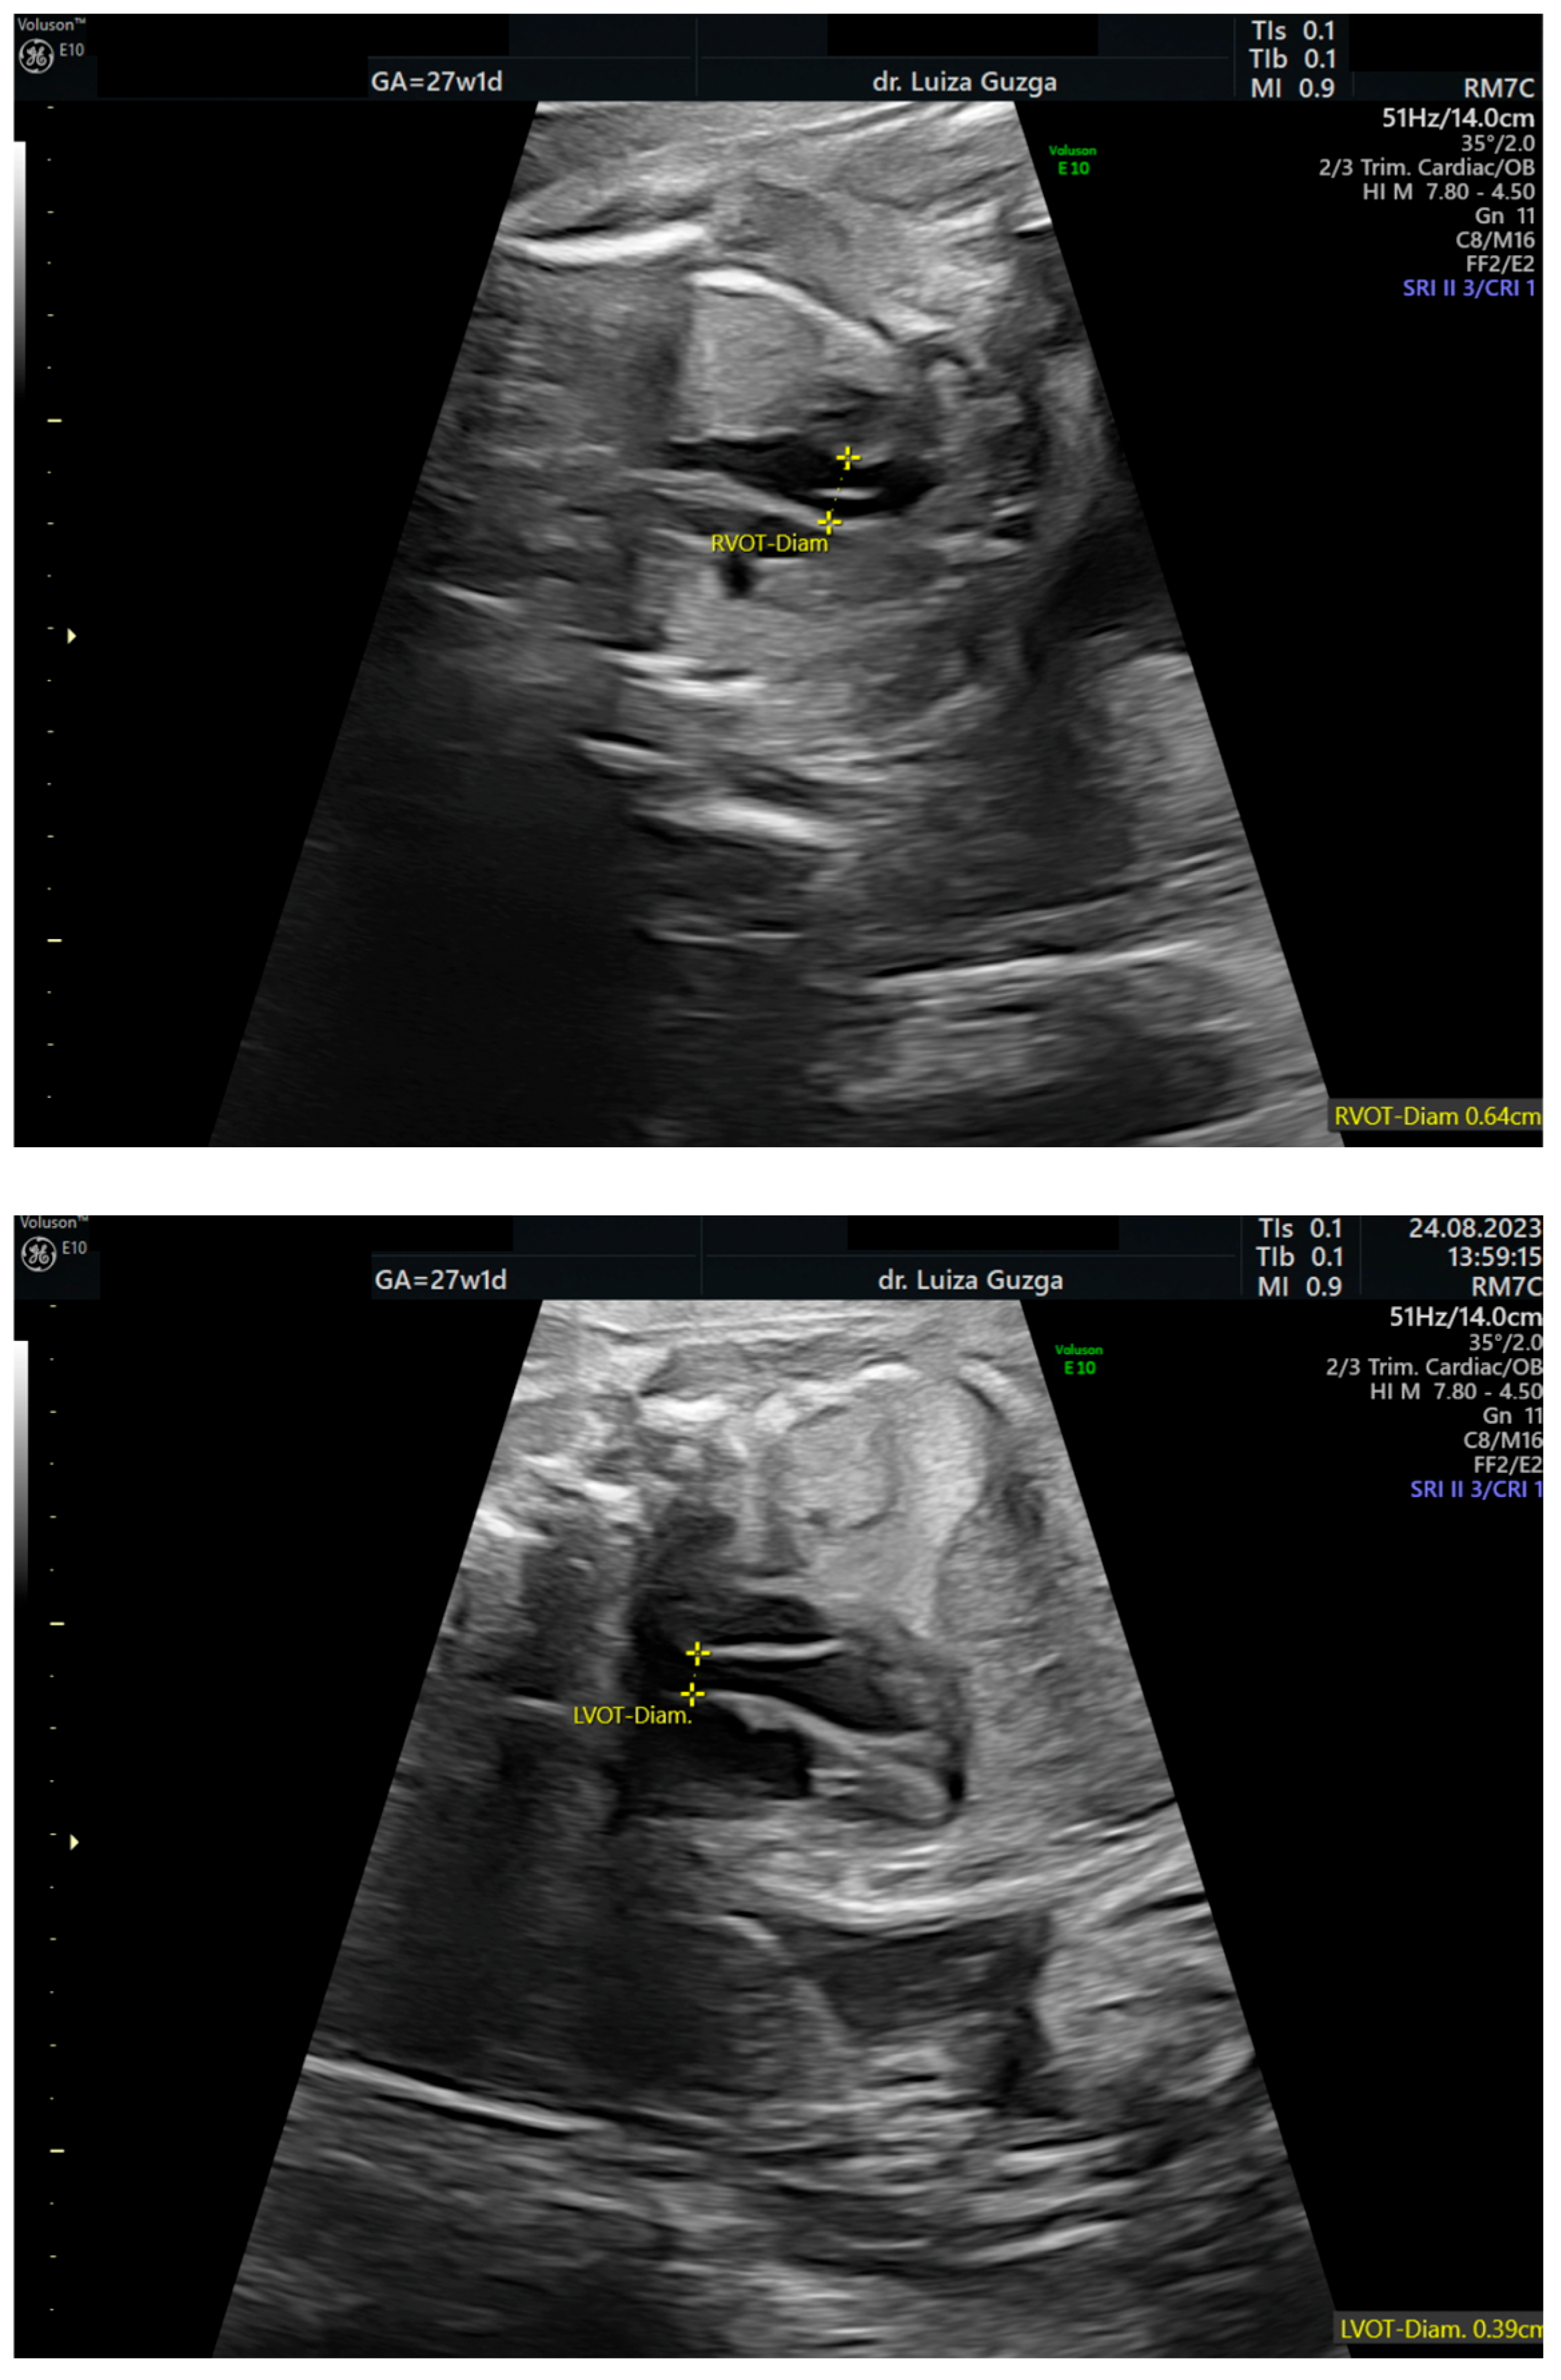

| Increased pulmonary valve echogenicity with normal PSV | - | + | + | ++ |

| Hypoplasia of the pulmonary artery (HPA) | x | ||||||||||||||

| Tetralogy of Fallot | x | ||||||||||||||